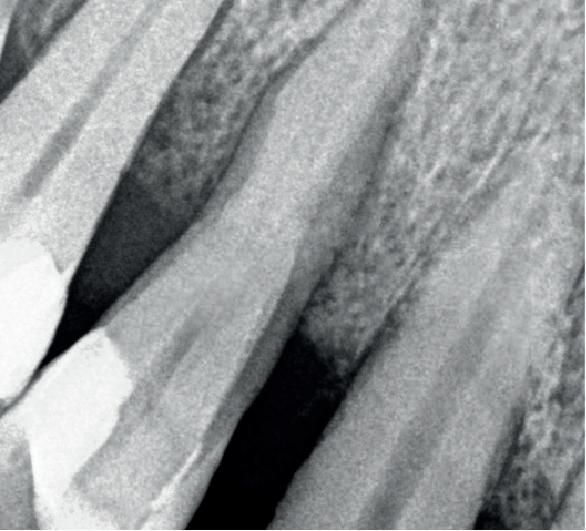

Een 48-jarige gezonde vrouw presenteerde zich in de nazorgfase 2 jaar na initiële behandeling met pockets van 6–7 mm en furcatieproblematiek bij de 47 en 46 (afbeelding 1.1 en 1.3). Bloeding bij sonderen was aanwezig, maar de patiente wilde geen chirurgische behandeling. Ze hield er een keurige mondhygiëne op na en kwam trouw iedere drie maanden voor nazorg.

De pockets werden onder lokale anaesthesie behandeld met een combinatie van ultrasoon en handinstrumentarium volgens de hierboven beschreven methode. De natriumhypochloriet/aminozuur-gel werd vijfmaal aangebracht en na iedere applicatie mechanisch verwijderd. Daarna werd de pocket gevuld met cross-linked hyaluronzuur.

Na 6 maanden was de pocketdiepte teruggebracht tot 3 mm en was er geen bloeding na sonderen waarneembaar. Een recessie van 2 mm was aanwezig. Röntgenologisch was er nieuw bot zichtbaar (afbeelding 1.2 en 1.4).

Een 62-jarige man hield in de nazorgfase een pocket van 8 mm met bloeding na sonderen mesiaal van de 36 ondanks 3-maandelijkse recall (afbeelding 2.1 en 2.3). De mondhygiëne was matig en plaque was aanwezig. Chirurgie werd geadviseerd, maar de pa-

tiënt wees dit af. Ook hier werd de pocket behandeld onder anaesthesie. De natriumhypochloriet/aminozuur-gel werd viermaal aangebracht, telkens gevolgd door ultrasone en handinstrumentatie. Tot slot werd cross-linked hyaluronzuur ingebracht. De mondhygiëne werd bijgestuurd en meneer werd gemotiveerd dagelijks interdentale ragers te gebruiken naast het poetsen.

Na zes maanden was de pocketdiepte teruggebracht tot 3 mm en was er geen bloeding na sonderen (afbeelding 2.2 en 2.4).